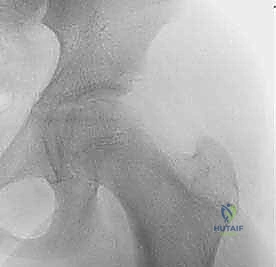

أ. النخر اللاوعائي (Avascular Necrosis - AVN)

هي المضاعفة الأكثر رعباً. تحدث عندما ينقطع الدم عن رأس عظمة الفخذ، مما يؤدي إلى موت الخلايا العظمية وتسطح رأس العظمة، وبالتالي خشونة مبكرة وتدمير للمفصل. المتابعة الدورية بالأشعة مع د. هطيف ضرورية لاكتشاف أي علامات مبكرة وعلاجها.

- الرنين المغناطيسي (MRI): يُستخدم نادراً في مرحلة التشخيص الأولي، ولكنه ضروري لاحقاً لمتابعة تدفق الدم واكتشاف أي علامات مبكرة للنخر اللاوعائي.